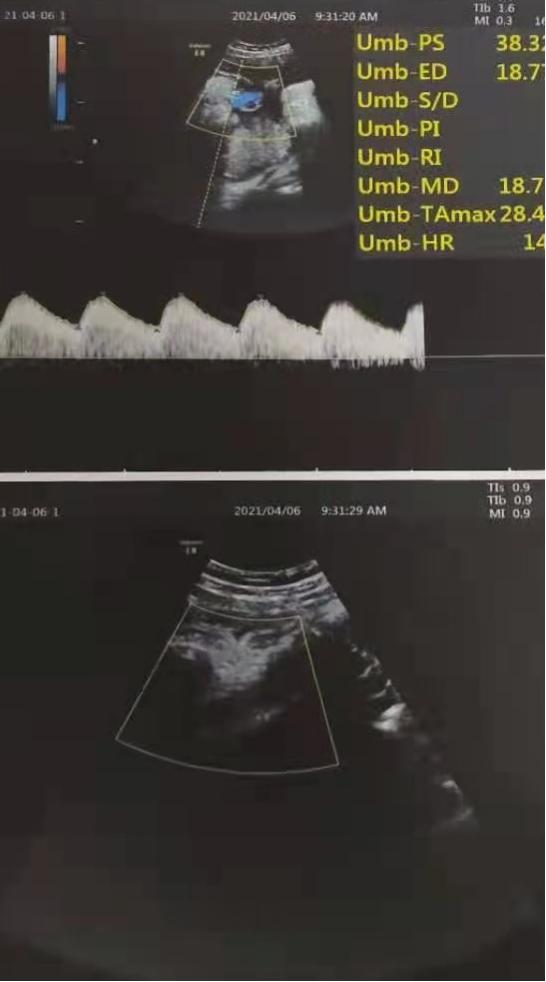

因为初步考虑诊断为巨大儿,所以我为患者完善了B超检查,结果提示:胎先露:头;胎盘位置:宮体前壁。成熟度3级,胎盘厚度38mm,下缘距宫颈内口尚远。胎心、胎动有。胎心率159bpm,律齐。诊断:宫内单活胎(39w3d孕)头位。

待术前相关检查结果回示正常后,我再次告知了孕妇及其家属麻醉风险及剖宫产过程中的风险后,为患者在硬膜外麻醉下行了子宫下段横切口剖宫产手术,手术过程顺利,胎儿健康。术后诊断:1.脐带绕颈 2.G3P1 39+5周剖宫产已产。

告知孕妇剖宫产手术及麻醉的风险后,患者本人及其家属仍然要求进行剖宫产,故完善术前相关检查,排除麻醉及手术禁忌症后,在硬膜外麻醉下为孕妇进行了子宫下段横切口剖宫产手术,手术过程顺利,成功娩出一活女婴,其外观无畸形,脐带长约60cm,绕颈一周,生命体征正常平稳。